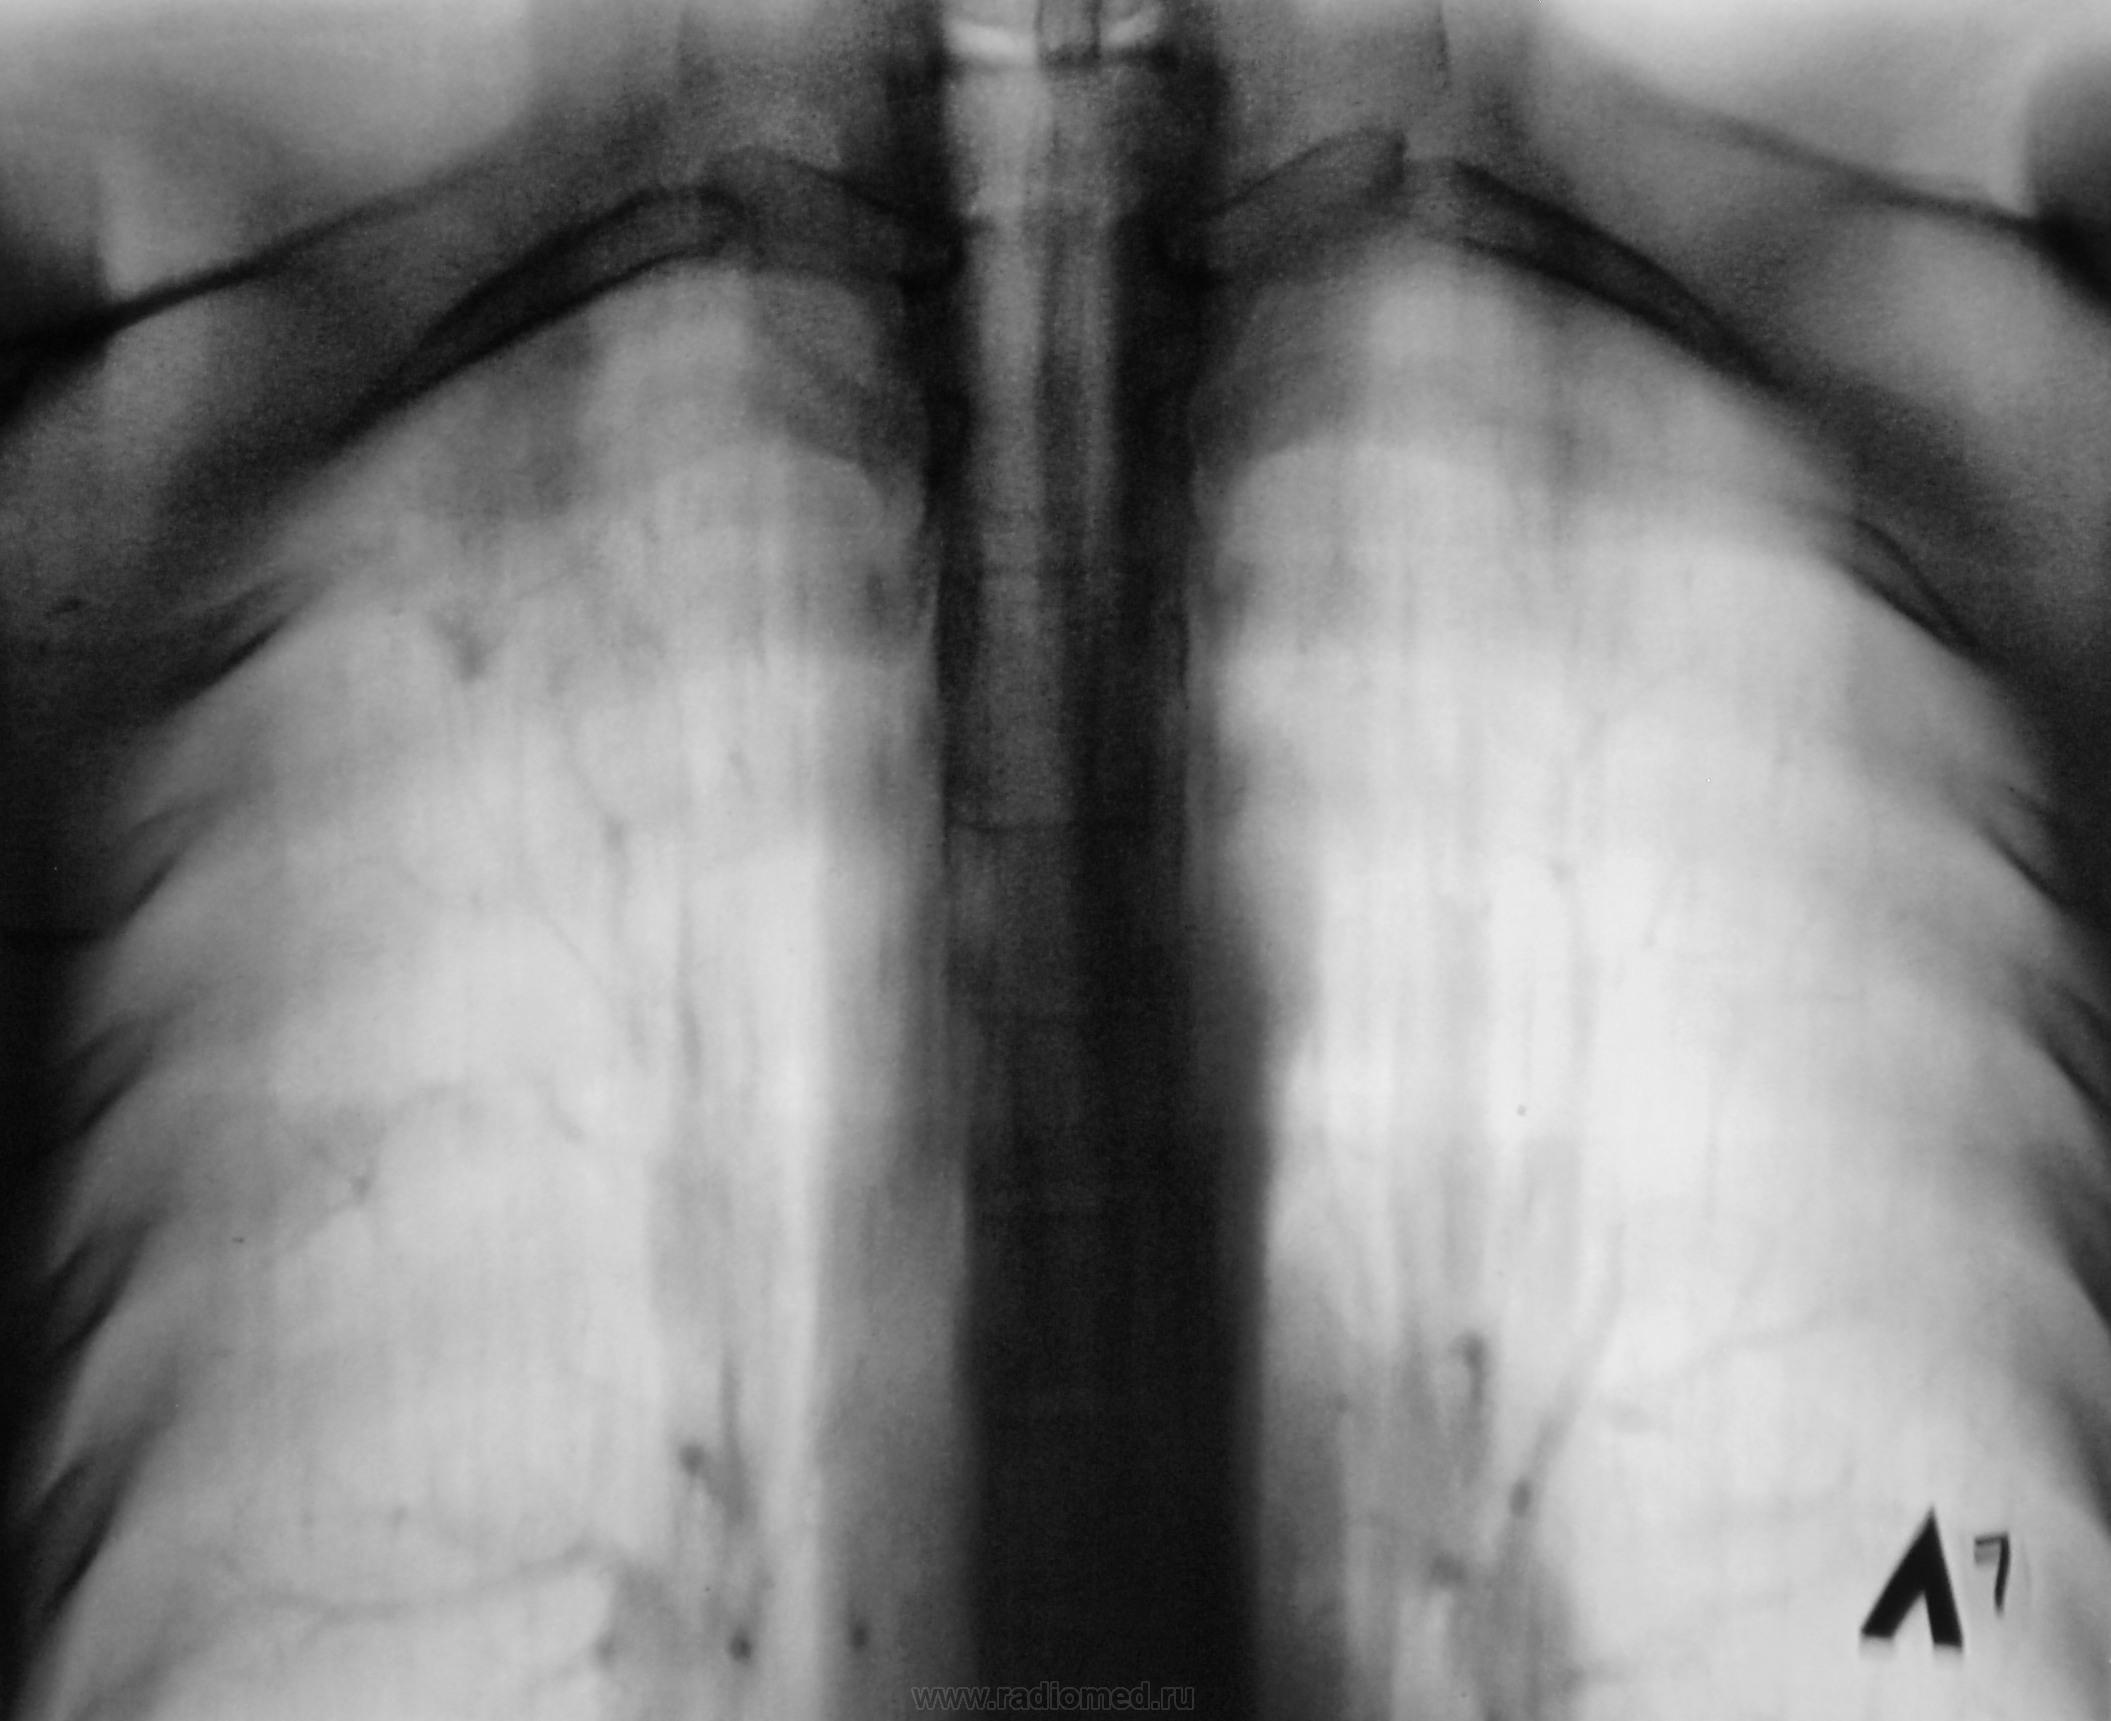

В протоколе написал - очаговый. Опять недоволен коллега фтизиатр, но на заметку взял... и через 6 месяцев на контроль прислал.

Но, шло время… и коллега фтизиатр через 6 месяцев направил пациента на «контроль» - «контроль контролей»…

Время шло, подросла и «крошка – фтиза», из очаговой в инфильтративную превратилась, да и «личико» в микроскопе показала…

И все-таки инфильтрат, который был еще на первом обзорном снимке в виде вытянутого овала в 1 м/р?? Больше этого никто не видит?